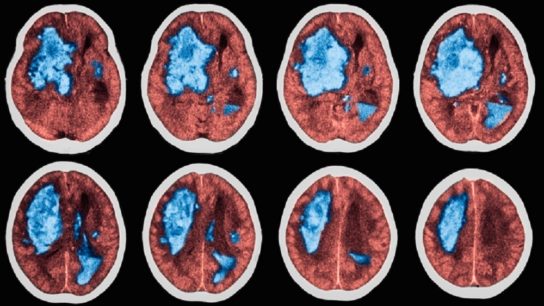

Two similarly controlled landmark trials provide conflicting results regarding the clinical guidelines for management of acute hypertension in individuals with intracerebral hemorrhage. However, focusing exclusively on blood pressure targets may obscure a critical finding.

Researchers find automated CT perfusion is an important tool in the triage and treatment decision making in acute ischemic stroke.